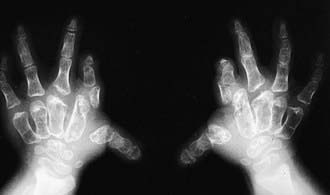

Radiographs reveal short and broad tubular bones with flared metaphyses and flat, irregular epiphyses (Fig. 688-2).

Figure 688-2 Radiograph of hands in diastrophic dysplasia. The metacarpals and phalanges are irregular and short. The first metacarpal is ovoid.

The capital femoral epiphyses are hypoplastic, and the femoral heads are broad. The ulnas and fibulas are disproportionately short. Carpal centers may be developmentally advanced; the first metacarpal is typically ovoid, and the metatarsals are twisted medially. There may be vertebral abnormalities, including clefts of cervical vertebral lamina and narrowing of the interpedicular distances in the lumbar spine.